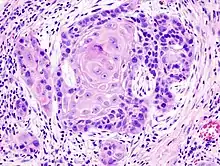

_squamous_cell_carcinoma_histopathology.jpg.webp)

Плоскоклітинний рак поширений в ділянці рота, включаючи внутрішню поверхню губ, язик, дно рота, ясна та тверде небо. Рак рота тісно пов'язаний із вживанням тютюну, особливо вживанням тютюну для жування, а також із вживанням міцного алкоголю. Рак в цій ділянці, особливо язика, частіше лікується хірургічним медом, ніж інші види раку голови та шиї.